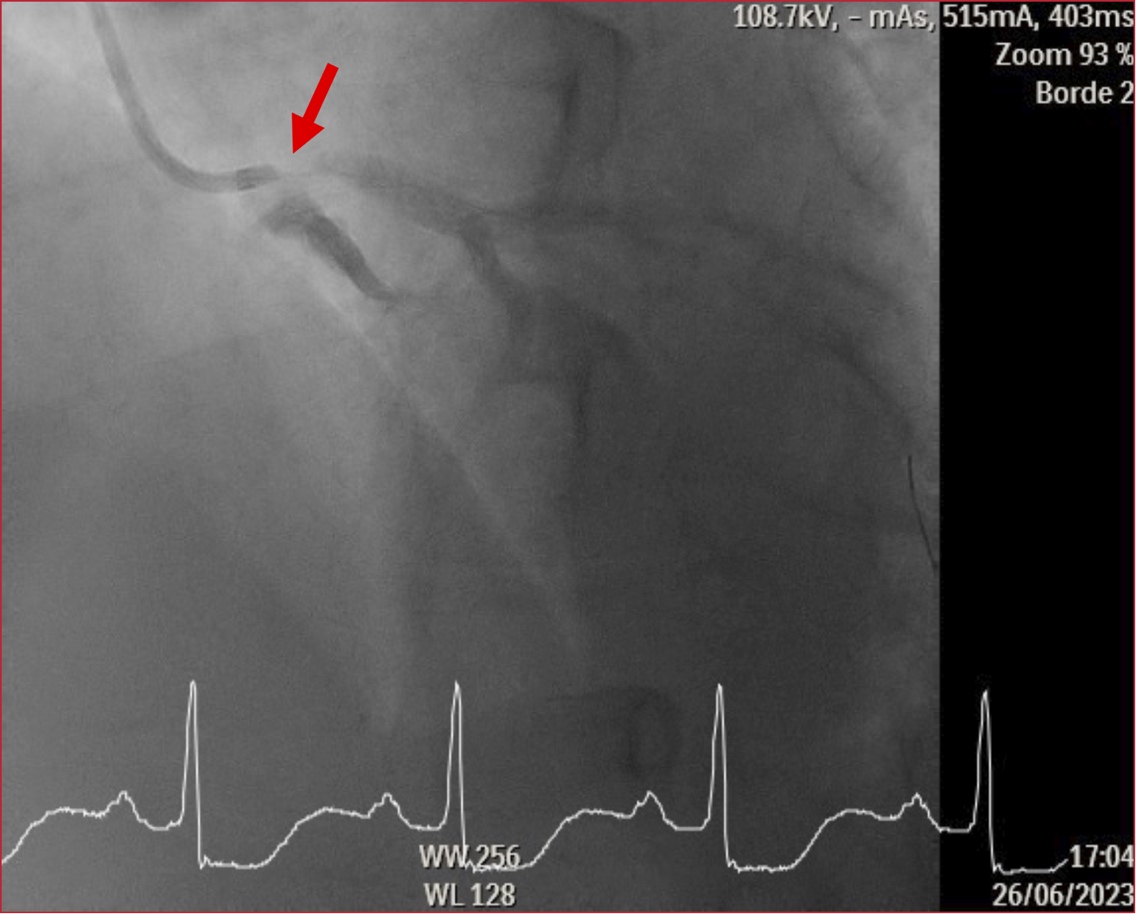

Return to Article Details High-risk non-ST-elevation acute coronary syndrome as a severe clinical manifestation of Cogan's Syndrome